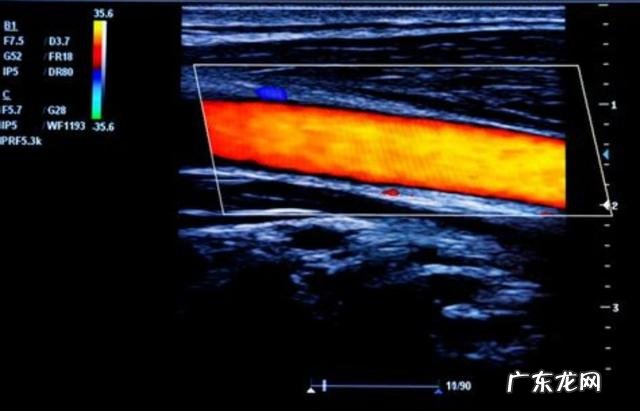

●另外如果存在着腰部的问题,也有可能导致患者出现下肢的无力,比如严重的腰椎间盘突出刺激到了神经根,而如果刺激的时间比较久,患者慢慢的疼痛麻木会减轻,无力的症状就会出现 。这种情况最好要进行腰椎的核磁检查,明确椎管内是否存在着压迫,另外也建议进行下肢肌电图检查,明确是否存在神经传导的问题,才能更好的选择zhi疗方案,帮助患者解决问题 。